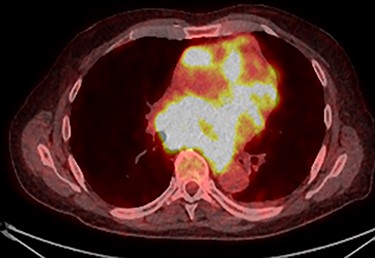

Further staging imaging was recommended by the radiology team. A CT head scan demonstrated no abnormalities, whereas CT chest–abdomen–pelvis (CAP) found significantly enlarged necrotic mediastinal lymph nodes with invasion into the pericardium and heart; bilateral adrenal nodules (suspicious for metastases) and appearances consistent with a lymphoproliferative disorder. The testicular biopsy found large lymphocytes with abundant cytoplasm and prominent nucleoli consistent with a diffuse large B-cell lymphoma (DLBCL). A positron emission tomography (PET) scan was organized at the request of the oncology team (Figs 4 and 5).

PET scan (coronal plane) showing intensely metabolically active lymphadenopathy on both sides with extra-nodal involvement through lymphoid tissue, adrenals and muscle.